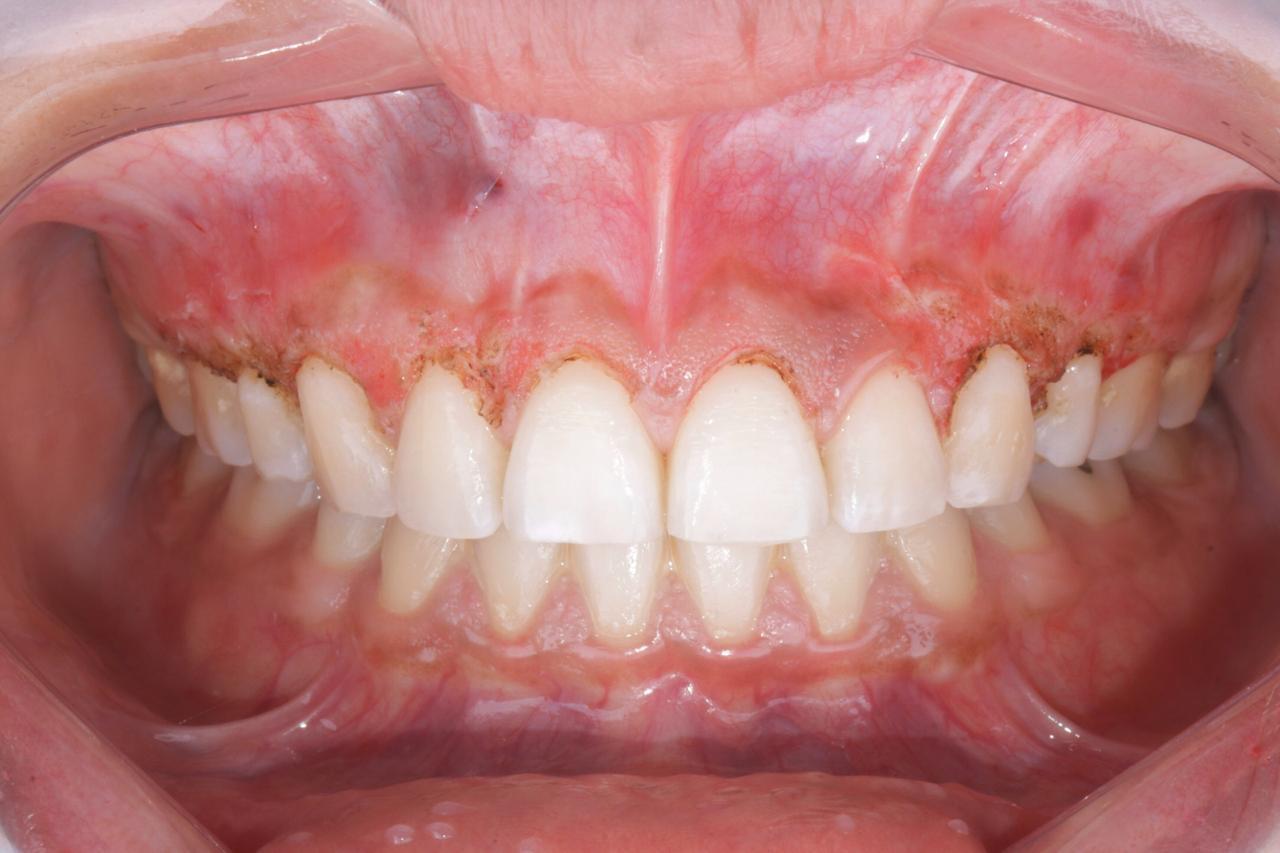

ANTES

antes Exceso de hueso y de encía despues Exceso de hueso y de encía

DESPUés

Después de tratamiento de ortodoncia presenta exceso de hueso y encía.